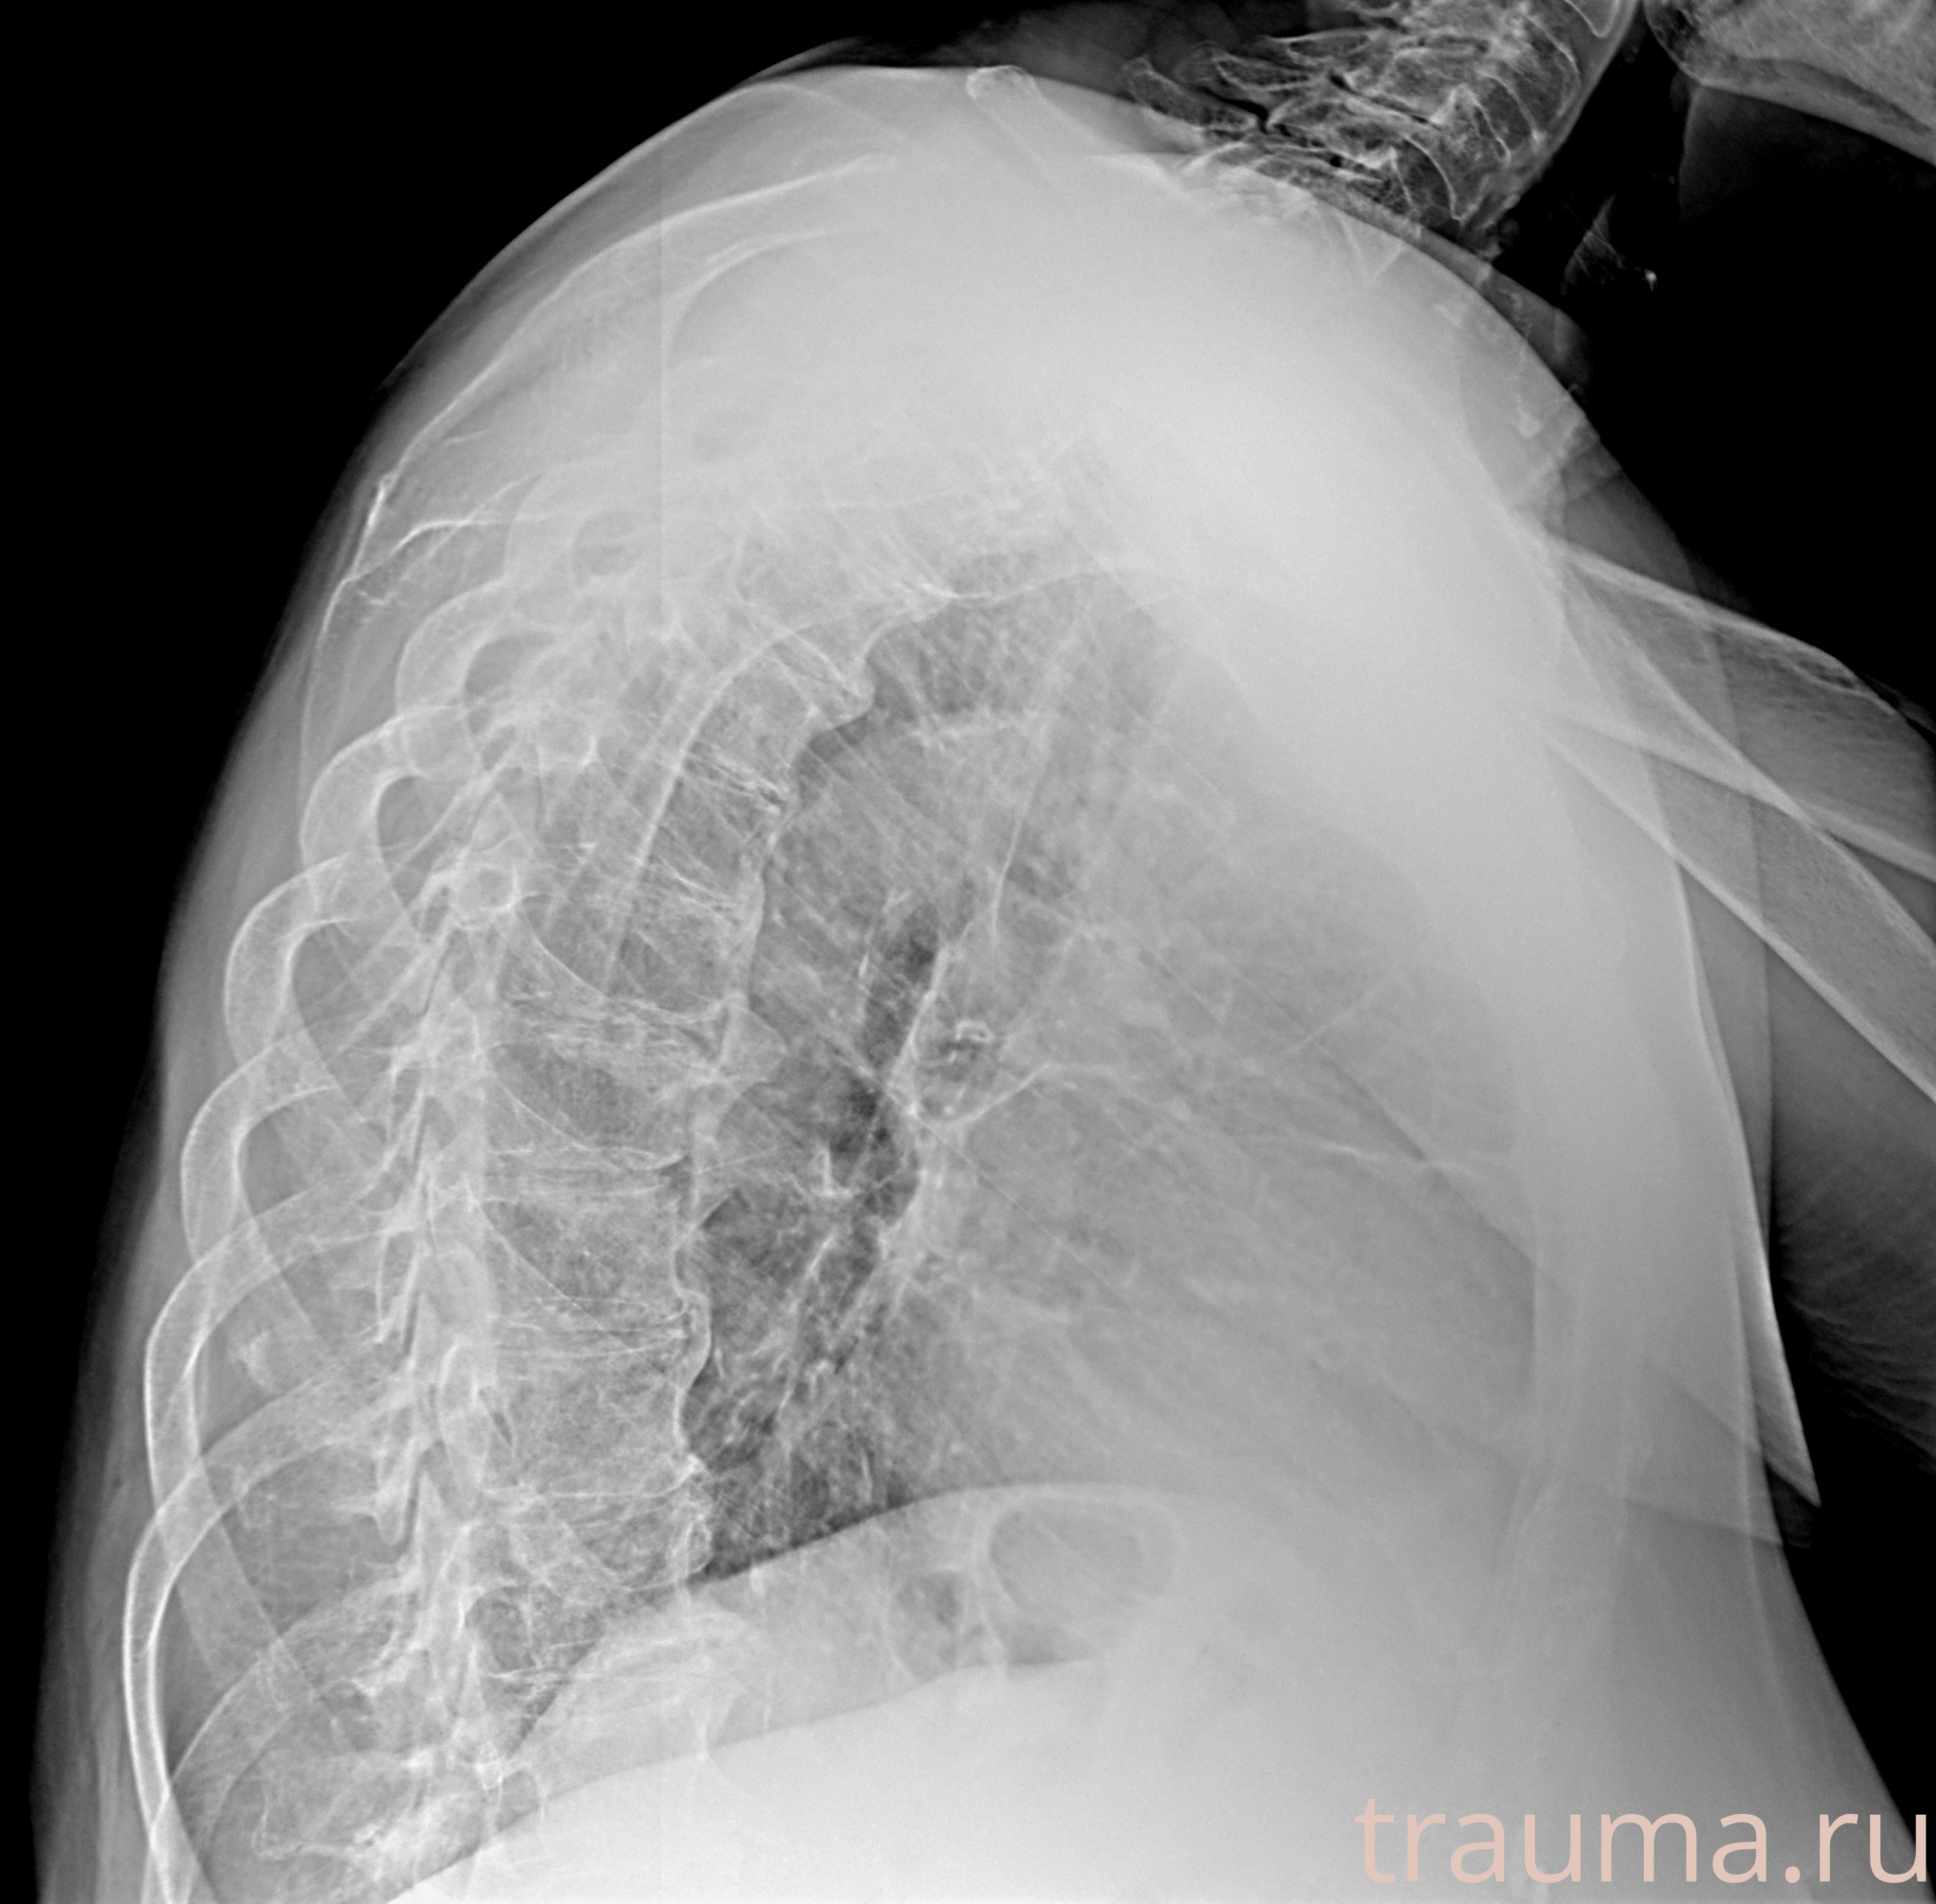

Рентгенограммы

Рентген на дому: по вашему адресу приезжает врач-рентгенолог, травматолог-ортопед с мобильным рентгеновским аппаратом, проводит диагностику травмы или заболевания, делает необходимые рентгенограммы, дает рекомендации по дальнейшему лечению. Получить качественные снимки в домашних условиях возможно благодаря уникальной методике, разработанной МосРентген Центром для института  Склифосовского